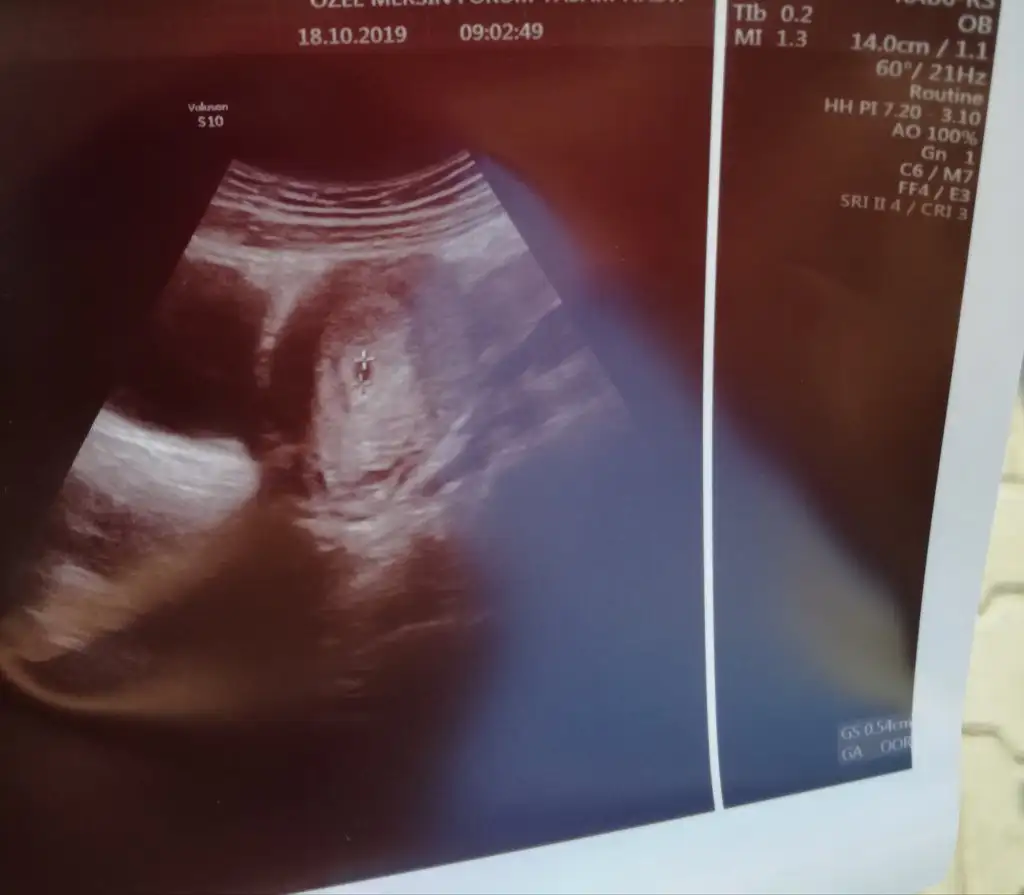

Kizlar ikizlerimin keselerini gordumm birer fatiha okur musuniuz benim.icin sagliklari icin

Oo maşallah fasulyeye darısı bizim gibi bekleyenlere senin içinde kalp atışı sıradakini duymayaGördüm çok şükür teyzesi

Bende bi hafta anca sonra görebilirim deseneGördüm çok şükür teyzesi

Amin amin inşallah sizlerde hayırlısıyla görürsünüz bizde kalp atışlarını duyarız. Hepimiz sağlıkla kucağımıza alırız.Oo maşallah fasulyeye darısı bizim gibi bekleyenlere senin içinde kalp atışı sıradakini duymaya